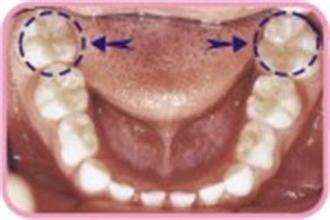

六龄齿是指儿童生长的恒磨牙,由于其通常在6岁左右萌发,故称之为“六龄齿”。六龄齿龋坏率高,拔除和患病的几率均高于其它牙齿。由于六龄齿对儿童的健康有极大的影响,因此要特别重视六龄齿的保护。那么,为什么六龄齿容易龋坏呢?

广州越秀圣贝口腔门诊部介绍:六龄齿是萌出时间早的恒磨牙,咬合面很大,承担着主要的咀嚼功能,容易积存食物残渣并形成菌斑,即便刷牙也不能将窝沟深度清洁,并且又由于窝沟内壁釉质薄,钙磷含量相对较少。因此,六龄齿是儿童龋齿中易发生龋坏的一颗牙齿。>>>预约牙管家更清楚